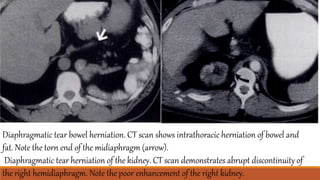

Diaphragmatic tear bowel herniation. CT scan shows intrathoracic herniation of bowel and

fat. Note the torn end of the midiaphragm (arrow).

Diaphragmatic tear herniation of the kidney. CT scan demonstrates abrupt discontinuity of

the right hemidiaphragm. Note the poor enhancement of the right kidney.

Diaphragmatic tear bowelherniation. CT scan shows intrathoracic herniation of bowel and fat. Note the torn end of the midiaphragm (arrow). Diaphragmatic tear herniation of the kidney. CT scan demonstrates abrupt discontinuity of the right hemidiaphragm. Note the poor enhancement of the right kidney.